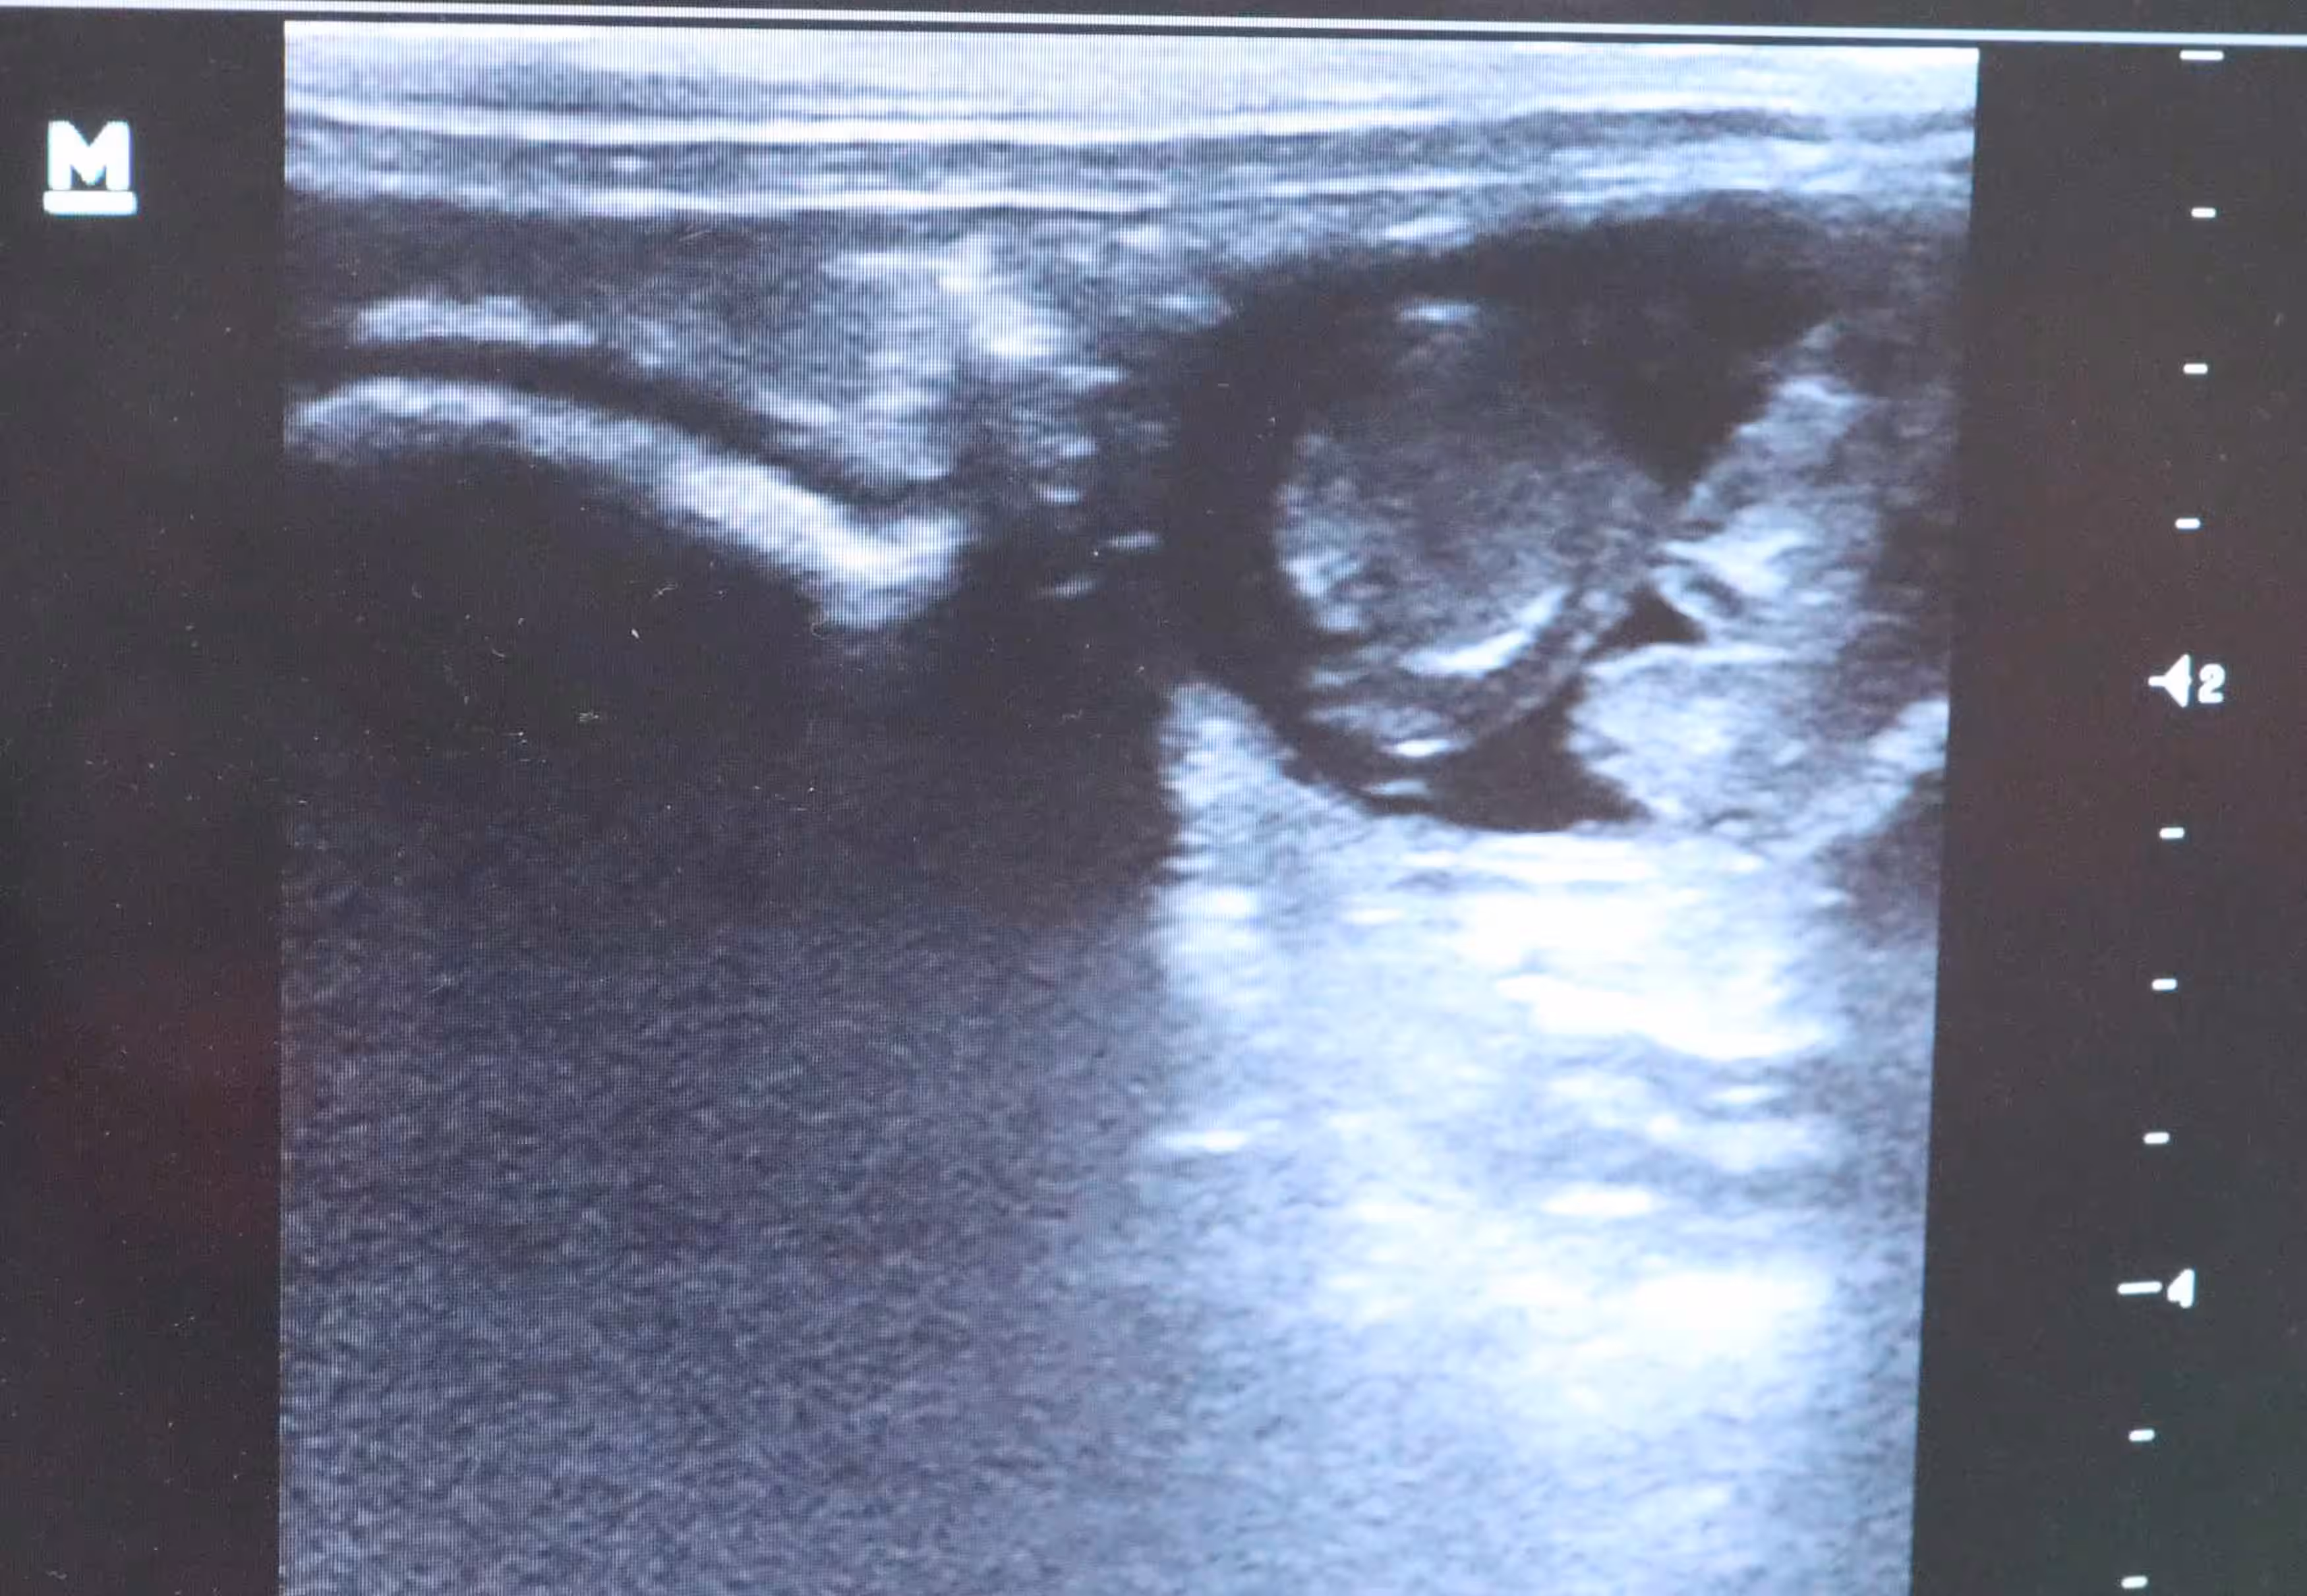

Sehr schlimm sahen die Genitalien vor allem der Männchen aus. Bissverletzungen an den Hoden waren bei fast allen Böcken vorhanden, einem fehlte sogar die Penisspitze. Bei einem Tier waren beide Hoden durch Bisse aufgeplatzt und das Hodengewebe ausgetreten. Diesen Rammler hat die Tierärztin gleich in Narkose gelegt und kastriert. Das Tier muss furchtbare Schmerzen gehabt haben.